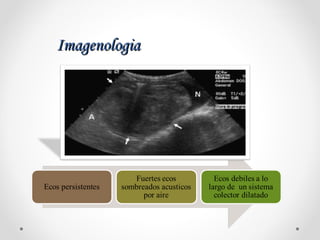

ImagenologiaImagenologia

Antibiotico con

drenaje del sistema

colector infectado